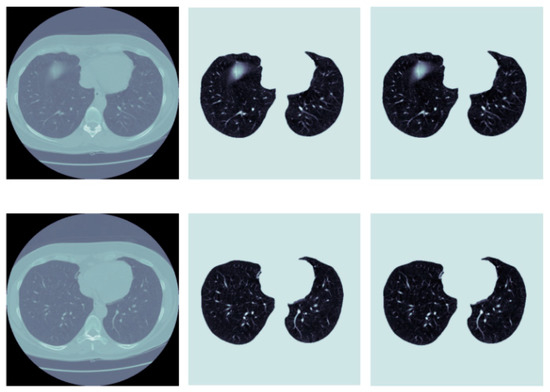

- Park, B.; Park, H.; Lee, S.M.; Seo, J.B.; Kim, N. Lung Segmentation on HRCT and Volumetric CT for Diffuse Interstitial Lung Disease Using Deep Convolutional Neural Networks. J. Digit. Imaging 2019, 32, 1019–1026. [Google Scholar] [CrossRef]